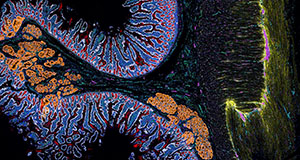

CODEX image of intestine courtesy of Dr. John Hickey from Stanford and Duke Universities